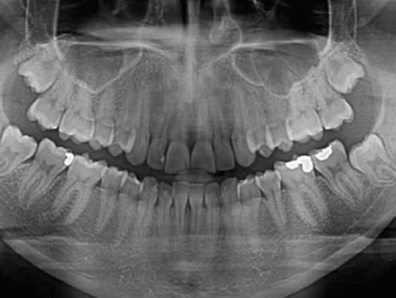

Una radiografía dental panorámica permite a tu dentista ver con todo detalle el estado de tu boca, dientes, hueso.

La odontopantomografía se conoce también como rayos X panorámicos, es un examen dental en 2D que permite capturar una imagen completa de la boca.

La radiografía dental ortopantomografía permite detectar problemas dentales mediante una imagen completa de los maxilares, la mandíbula y los dientes.

- Permite observar con gran nitidez los dientes, la mandíbula y sus articulaciones, el área nasal y los senos maxilares.